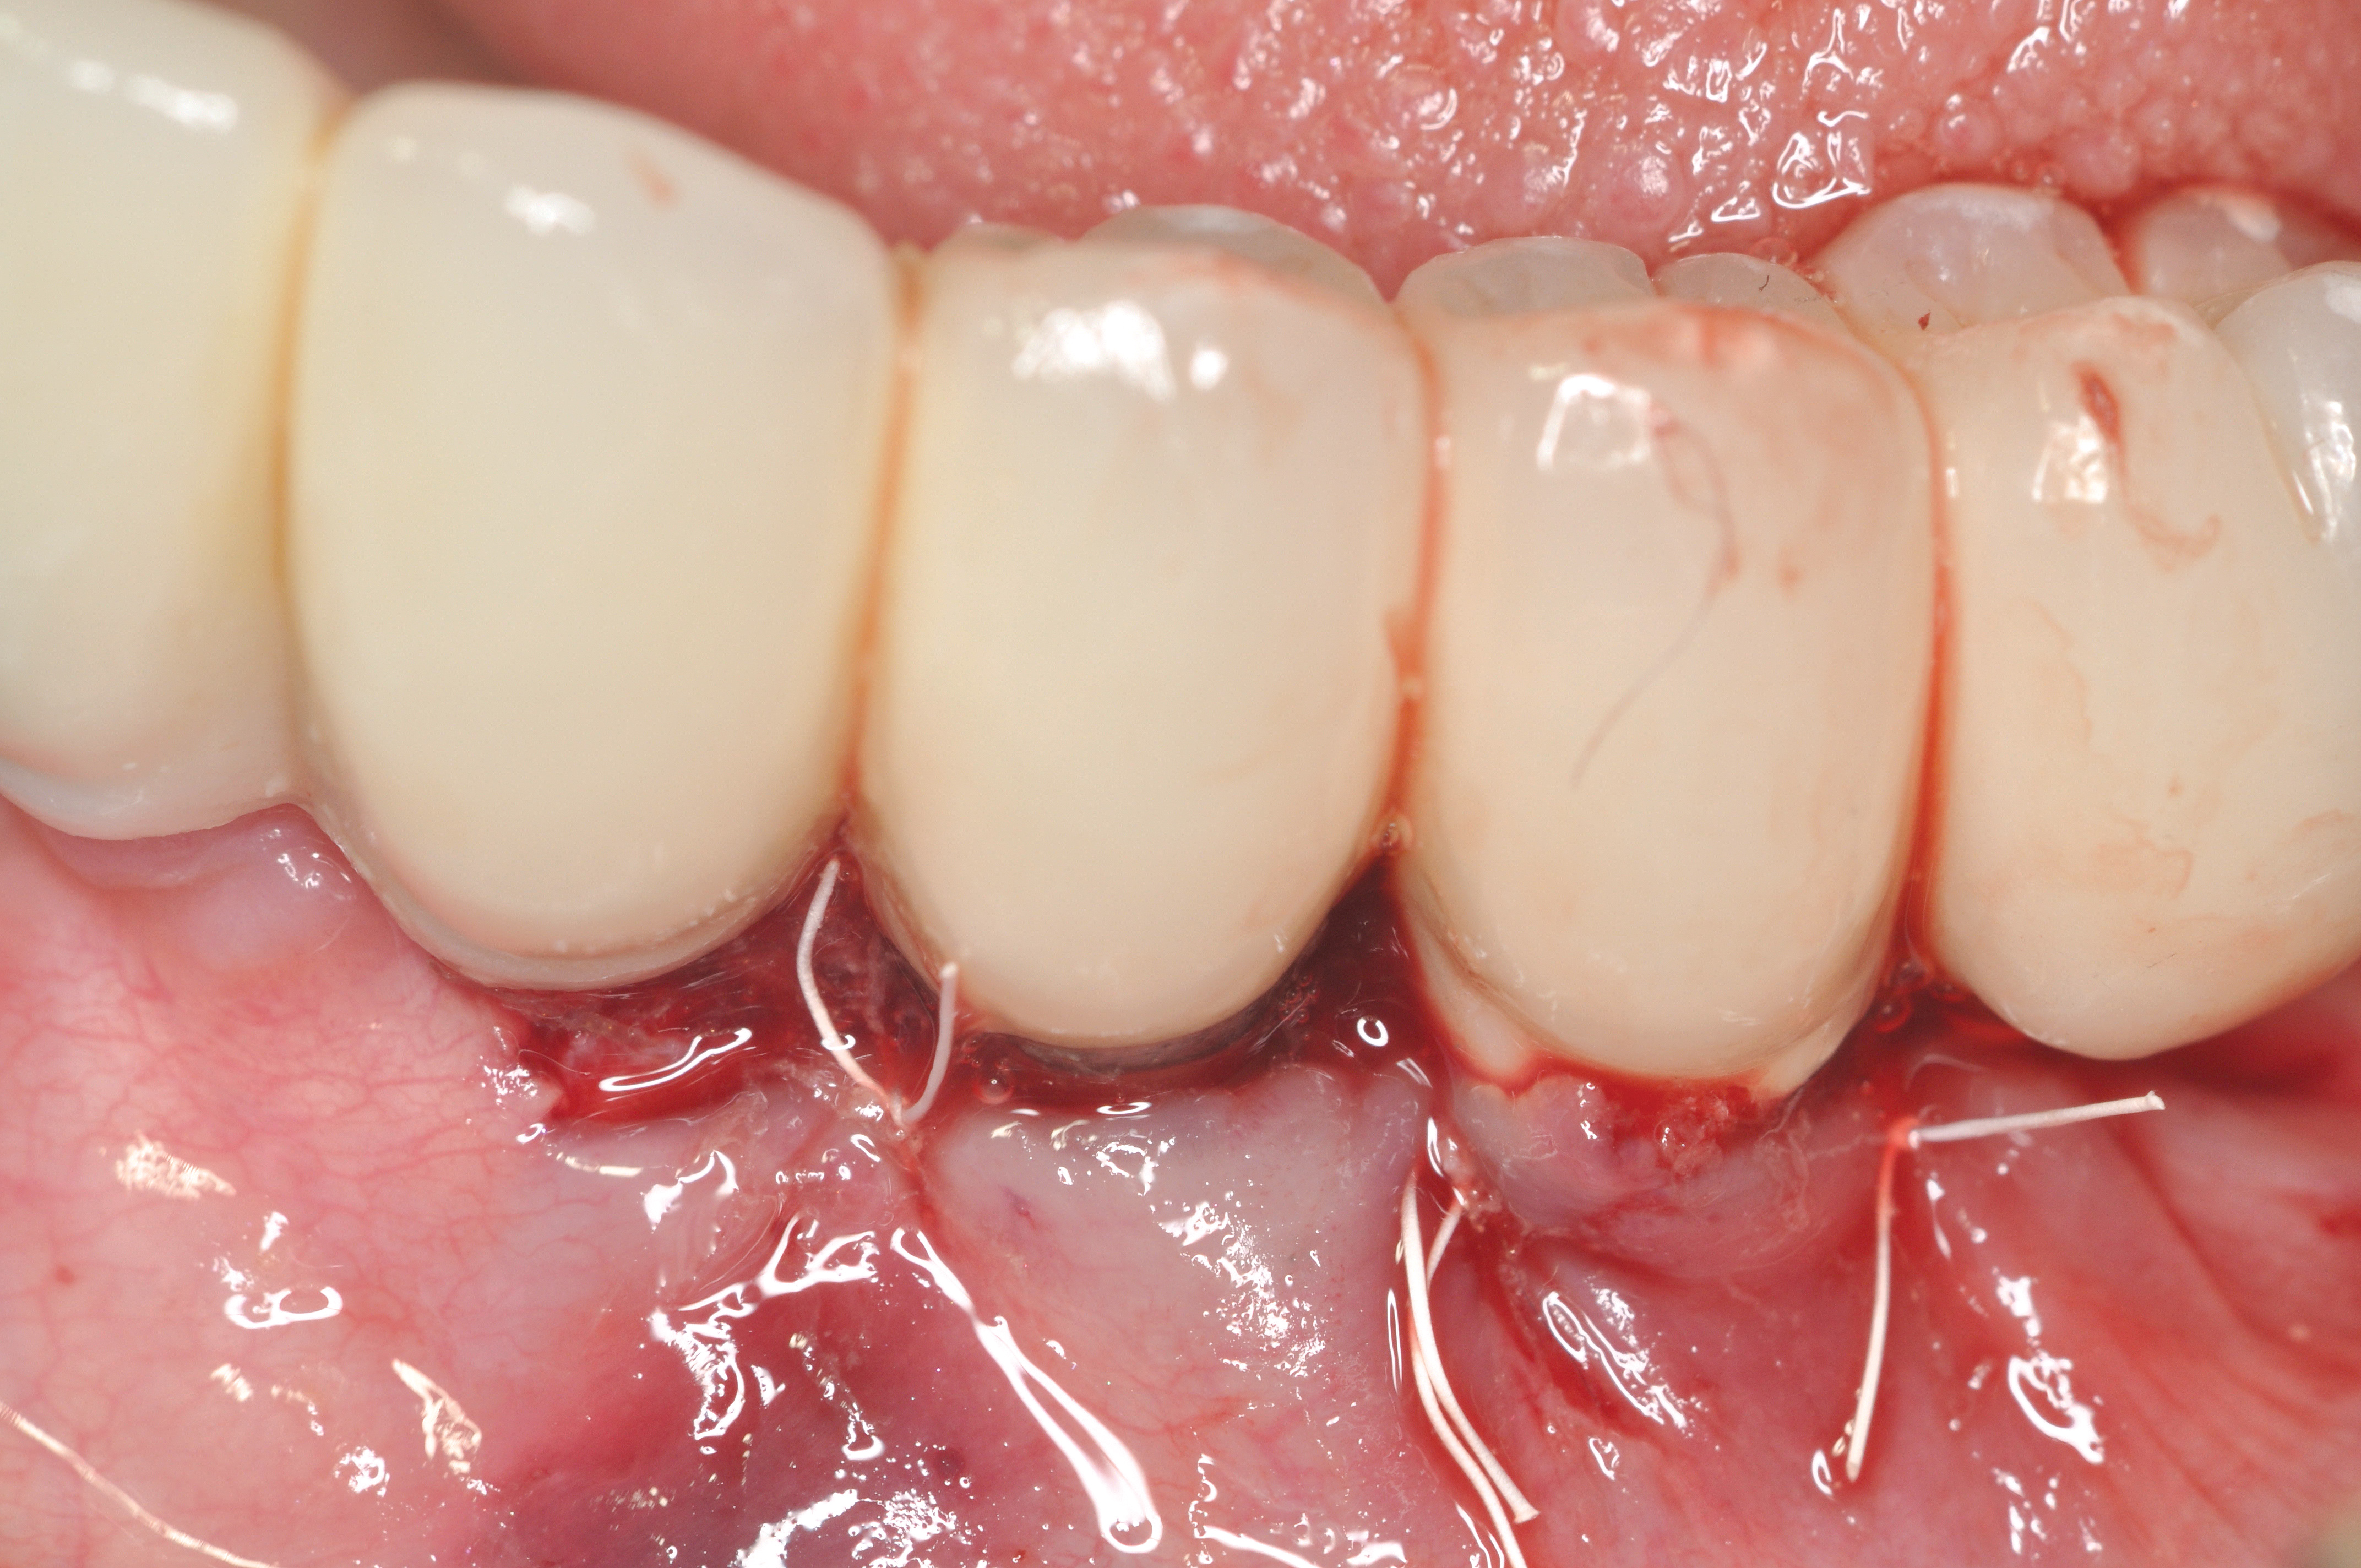

Studies have demonstrated that much like teeth, dental implants have a certain biologic dimension established following their healing after surgery and much of this understanding comes from evidence obtained from animal studies.18,19 However, in a seminal article on implant placement, Salama et al20 further highlighted the concept of bone surrounding an implant. A violation to the dimension of bone present in any of the buccal-palatal, mesial-distal, or apical-coronal directions will lead to bone loss (Figure 5 through Figure 7). This relates to the blood supply necessary to maintain the bone surrounding a dental implant. If an implant is placed in a position in which the minimal bone dimensions are not respected, crestal loss can be anticipated. While this may represent a contained lesion and remain static, it may not always be the case. In implants designed with a surface roughened to the top, suboptimal plaque control can lead to ongoing bone loss, because the exposed roughened surface is challenging to clean and will act as a plaque-retentive feature.21

Fig 5. Clinical view of implants depicting suggested bone loss. Plaque was present throughout, and the distal-most implant had substantial purulent exudate.

Figure 5

Fig 6. From a more anterior view, it was apparent that the labial positioning of these implants was outside the alveolar housing.

Figure 6